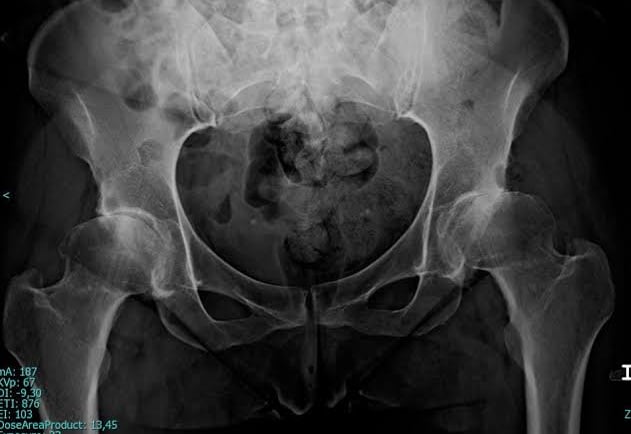

Radiografías, más utilizadas cuando el niño crece y los huesos se desarrollan más